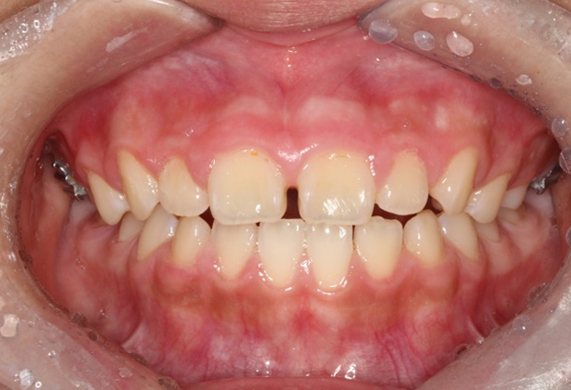

얼굴 골격의 성장에 문제가 있는지를 파악하기 위한 적절한 시기는 초등학교 입학 전인 6-7세경입니다. 이때는 유치에서 영구치로 교환되는 시기로서 부정교합 여부가 결정되는 중요한 시기이므로 이 시기를 잘 관찰하여 부정교합을 예방하는 것 또한 중요합니다. 교정의 정확한 시기는 6개월 간격으로 치과에 정기적으로 내원하여 성장 분석을 받은 후 결정하는 것이 좋습니다.